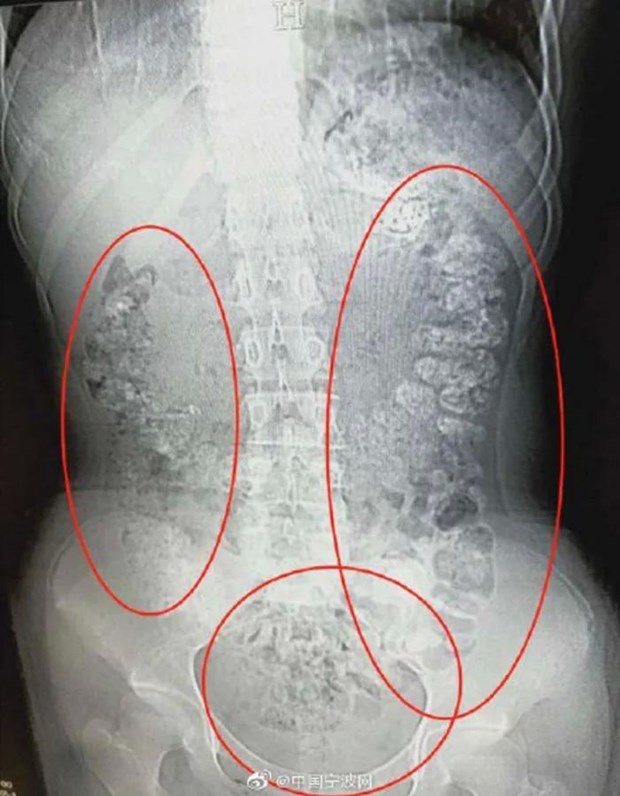

Các hạt trân châu chưa được tiêu hóa hết.

Phát hiện bụng cô bé phình to bất thường, các bác sỹ đã quyết định đưa bệnh nhân này đi chụp cắt lớp. Kết quả chụp cắt lớp cho thấy hàng trăm vật thể nhỏ hình tròn nằm trong khắp các cơ quan nội tạng, từ dạ dày, đại tràng, ruột và hậu môn.

Sau khi cùng nhau thảo luận, các bác sỹ kết luận những vật thể nhỏ này là các hạt trân châu chưa được tiêu hóa hết. Bác sỹ Zhang Louwei đã hỏi cô bé xem bệnh nhân có ăn gì khó tiêu trong vài ngày qua hay không. Cô bé thừa nhận đã uống một cốc trà sữa từ 5 ngày trước khi nhập viện.

Tuy nhiên, bác sĩ Zhang cho rằng số hạt trân châu này được tích tụ do cô bé đã uống trà sữa trân châu trong một thời gian dài.

Các hạt trân châu vẫn mắc kẹt trong hệ tiêu hóa.